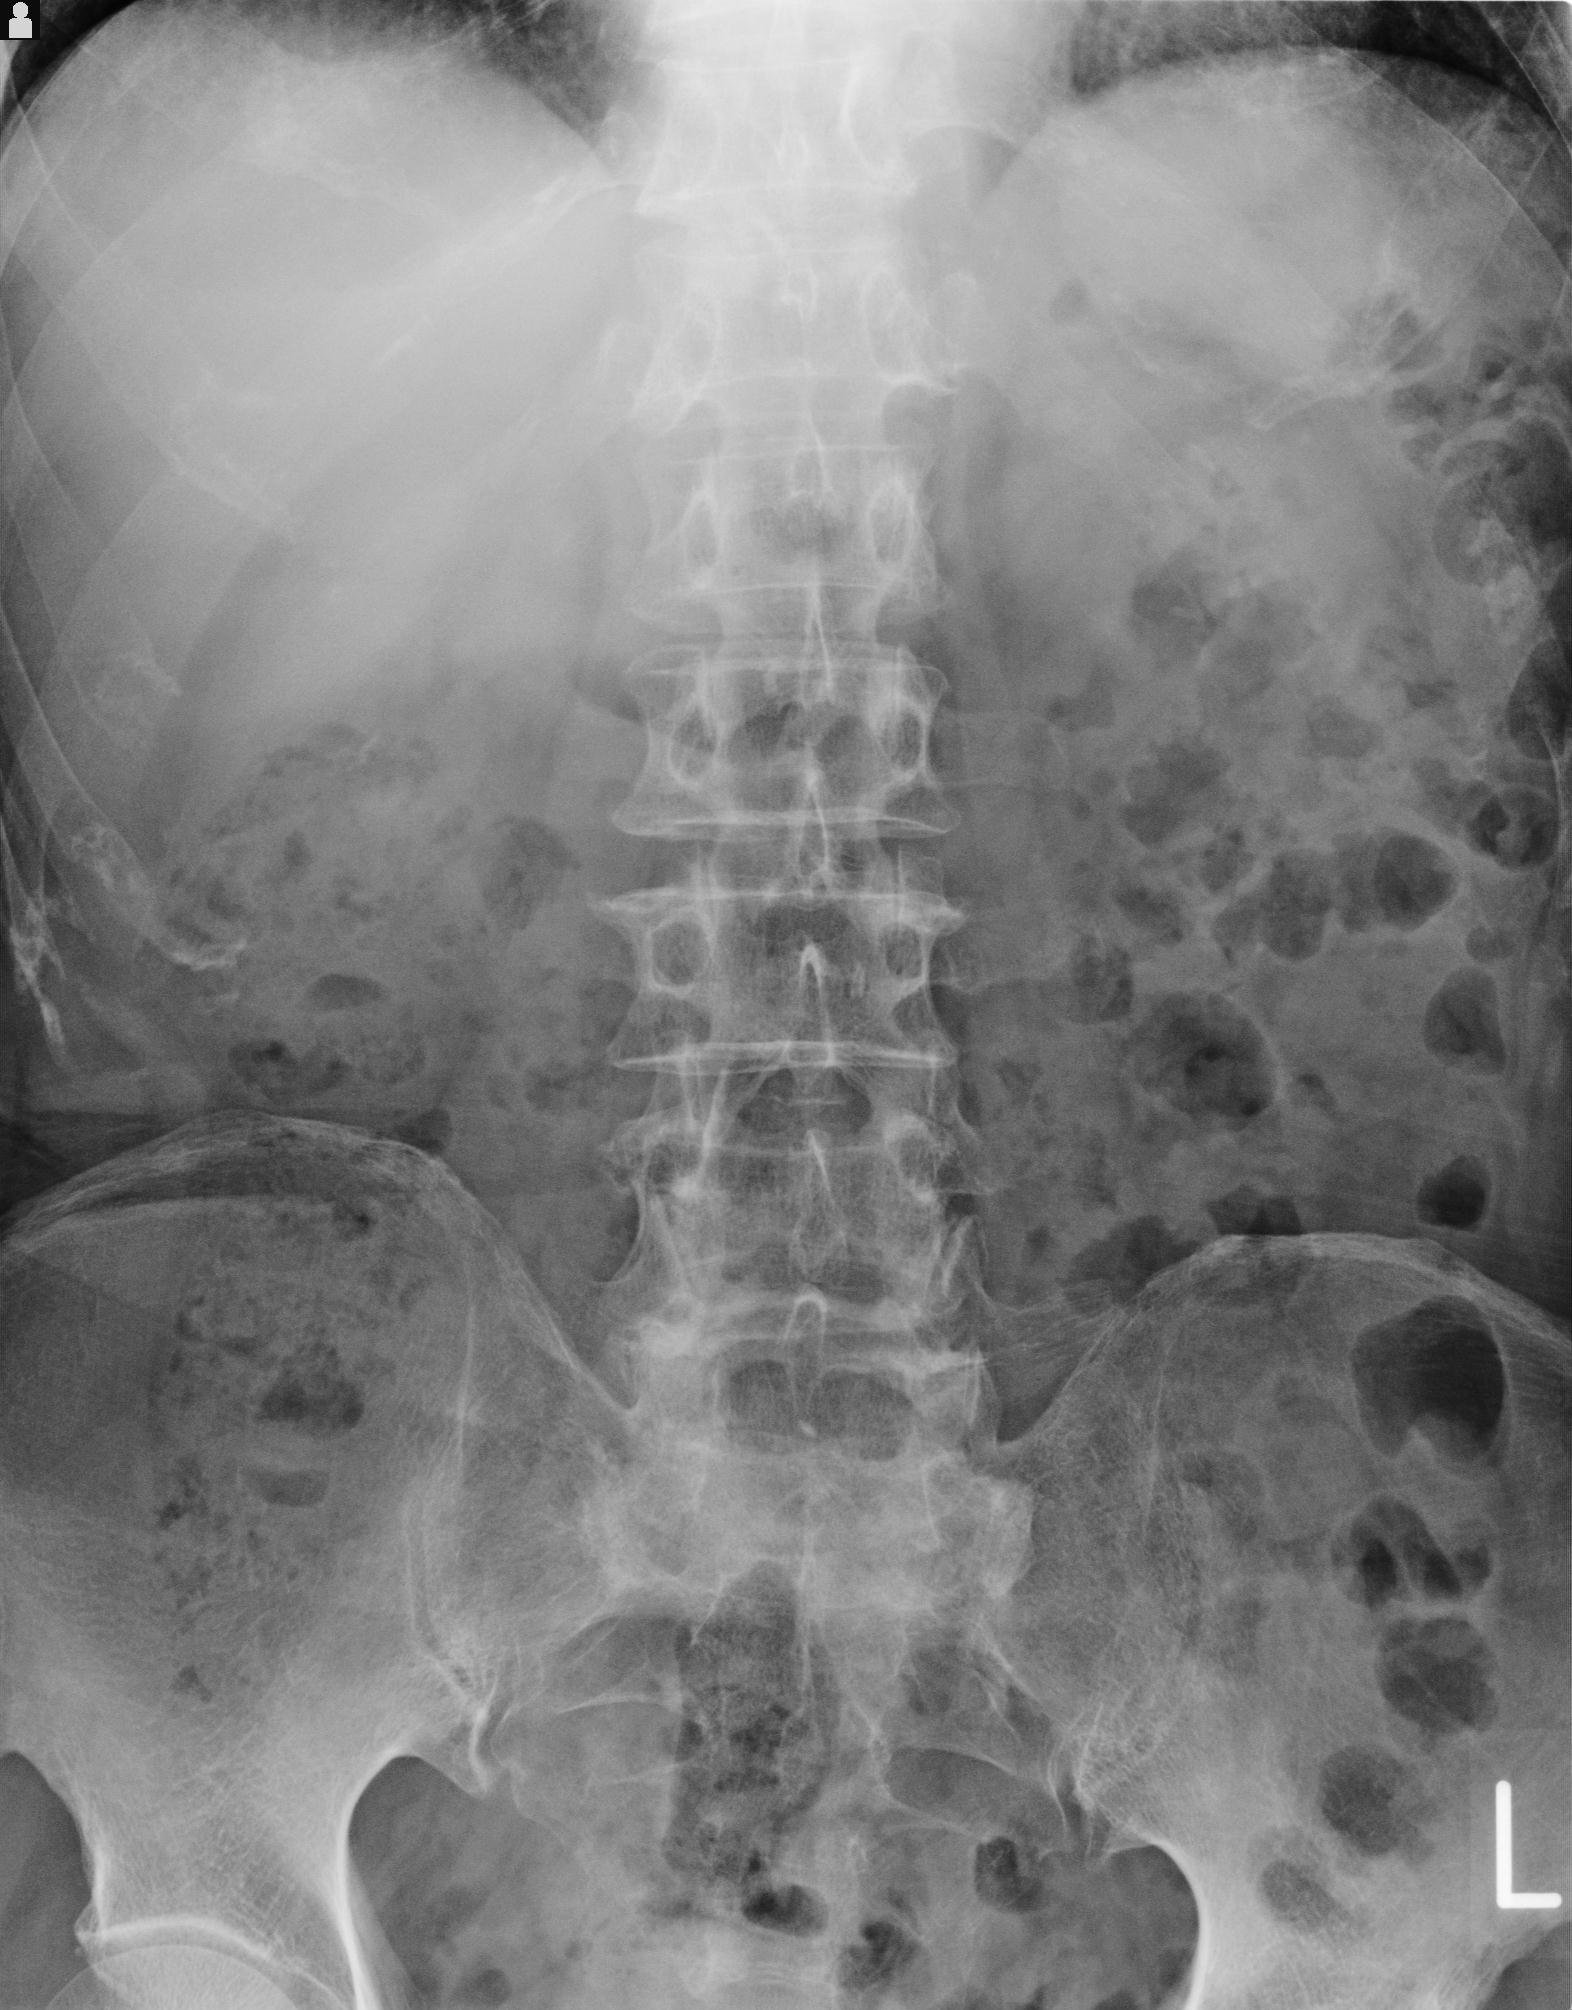

100703 1/27 両股正面+軸 1/29 両股正面+軸 94歳女性 パンソンロン